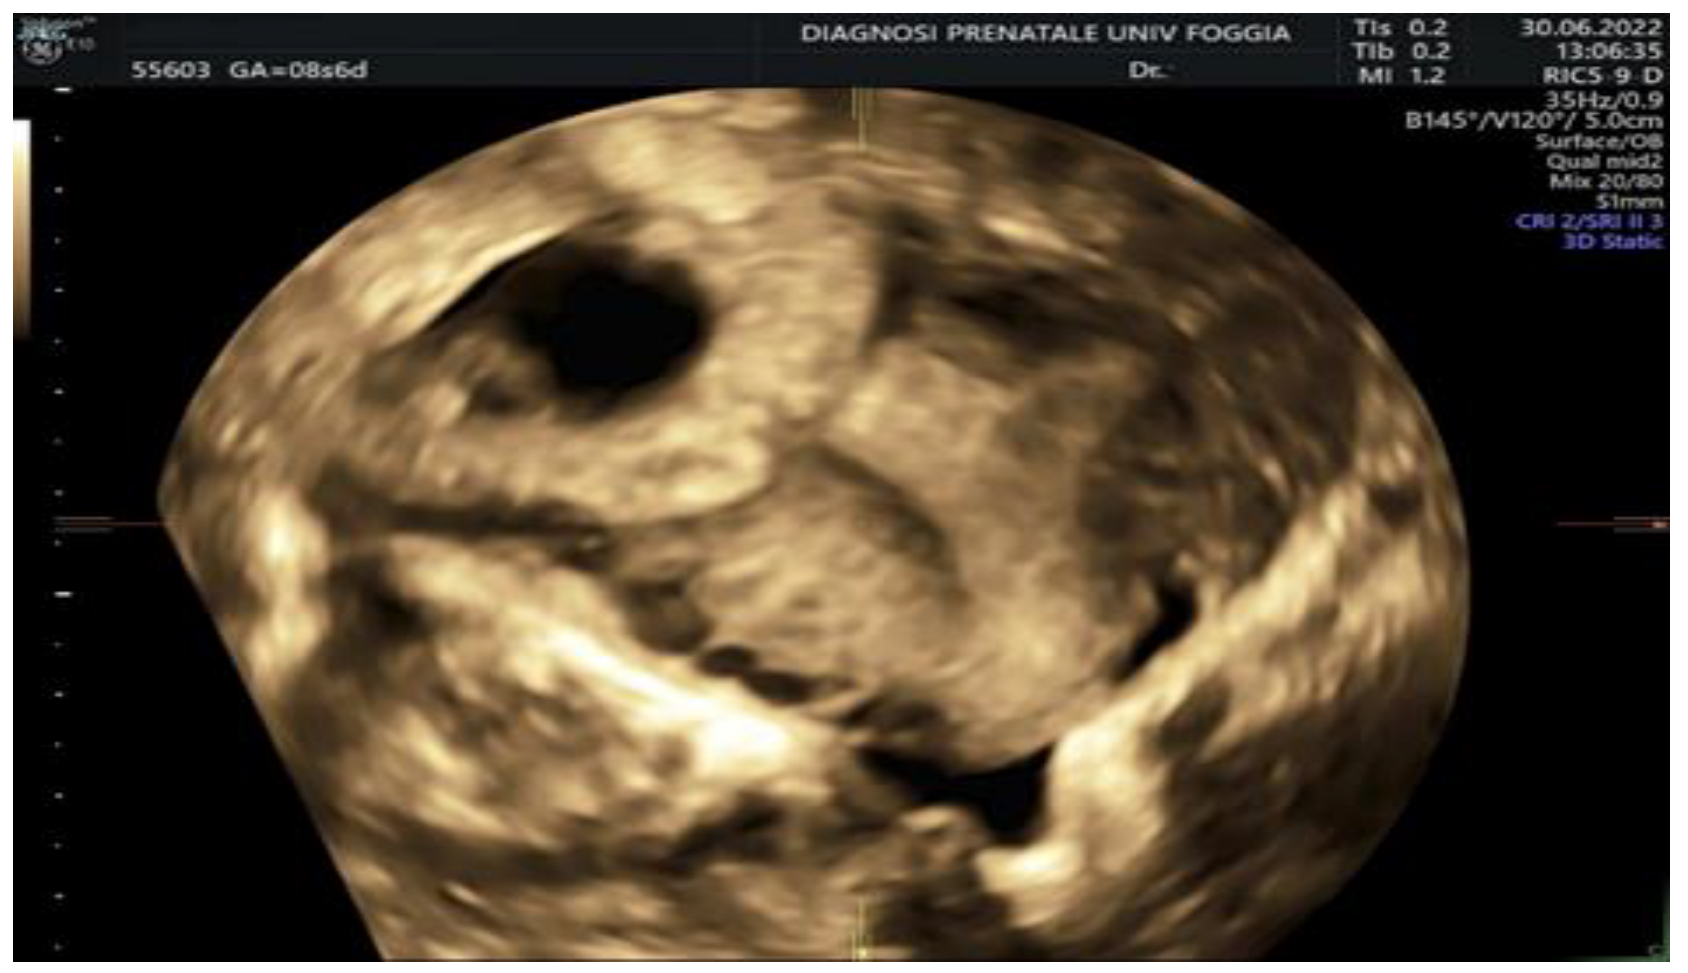

2. Case Presentation